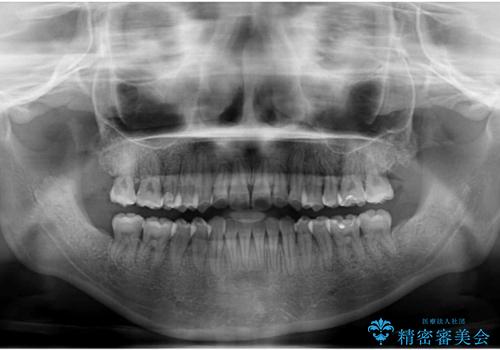

ハーフリンガル 反対咬合の改善

下顎の歯列全体を後方に動かす場合、さまざまリスクを伴うため慎重に行う必要があり、さらには移動量に限界があるため、治療計画は無理のないものとしなければなりません。

下顎左右の奥にアンカーボルトを使用して、無理のない範囲で後方に移動させ、きれいに仕上げることができました。